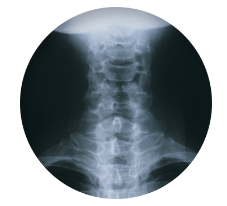

목 디스크 증상 팔저림에 대해 알아봐요 목 디스크 증상 원인 치료방법 및 목 디스크 팔저림에 대해 알아보도록 하겠습니다.

목 디스크는 목의 디스크(경추 디스크)에서 발생하는 질환으로, 경추 디스크 사이의 연골판이 터져 디스크 내부 물질이 경추 신경을 자극해 통증이나 저림증 등의 증상을 유발합니다. 목 디스크는 일상생활에서의 안 좋은 자세나 과도한 운동, 부상 등이 원인이 될 수 있으며, 나이가 들수록 발생 확률이 높아집니다. 목 디스크의 증상으로는 목 부위의 통증, 팔의 저림, 근육 약화 등이 있으며, 증상이 심각한 경우 수술 등의 치료가 필요할 수 있습니다. 그러나 대부분의 경우 치료 없이도 시간이 지나면 증상이 호전되는 경우가 많습니다.